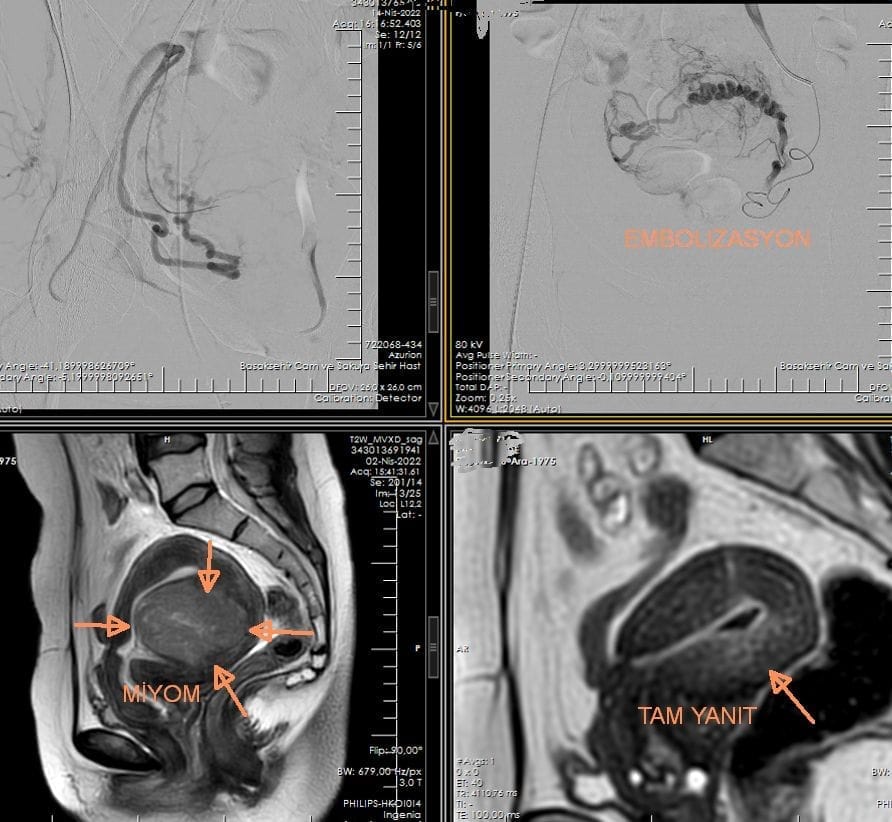

Miyom embolizasyonu, rahimde bulunan iyi huylu tümörler olan miyomların kan akışını keserek küçülmesini sağlayan minimal invaziv bir girişimsel radyoloji yöntemidir. Cerrahiye gerek kalmadan miyom kaynaklı kanama, ağrı ve bası şikâyetlerini azaltmada etkilidir.

İşlem sırasında kasık veya bilekten girilerek rahim arterlerine ulaşılır ve miyomu besleyen damarlar mikrokateter aracılığıyla tespit edilir. Ardından özel embolizan maddeler enjekte edilerek damarlar kalıcı olarak tıkanır ve miyomun küçülmesi sağlanır.

Miyom embolizasyonu öncesinde ultrason, manyetik rezonans görüntüleme ve gerekli laboratuvar testleri ile miyomun boyutu, sayısı ve yerleşimi değerlendirilir. İşlem genellikle lokal anestezi ve sedasyon altında yapılır, düşük komplikasyon riski taşır.

| İşlem Açıklaması | Girişimsel radyologlar tarafından yapılan anjiografik işlemde, uterin arterler aracılığıyla miyomları besleyen kan damarlarına küçük partiküller enjekte edilerek kan akışı durdurulur |

- Kateter yoluyla kontrast madde enjekte edilir.

- Anjiyo kullanılarak miyomları besleyen atardamarlar tespit edilir.

- Uzman bu damarlara embolizasyon için minik parçacıklar enjekte eder.